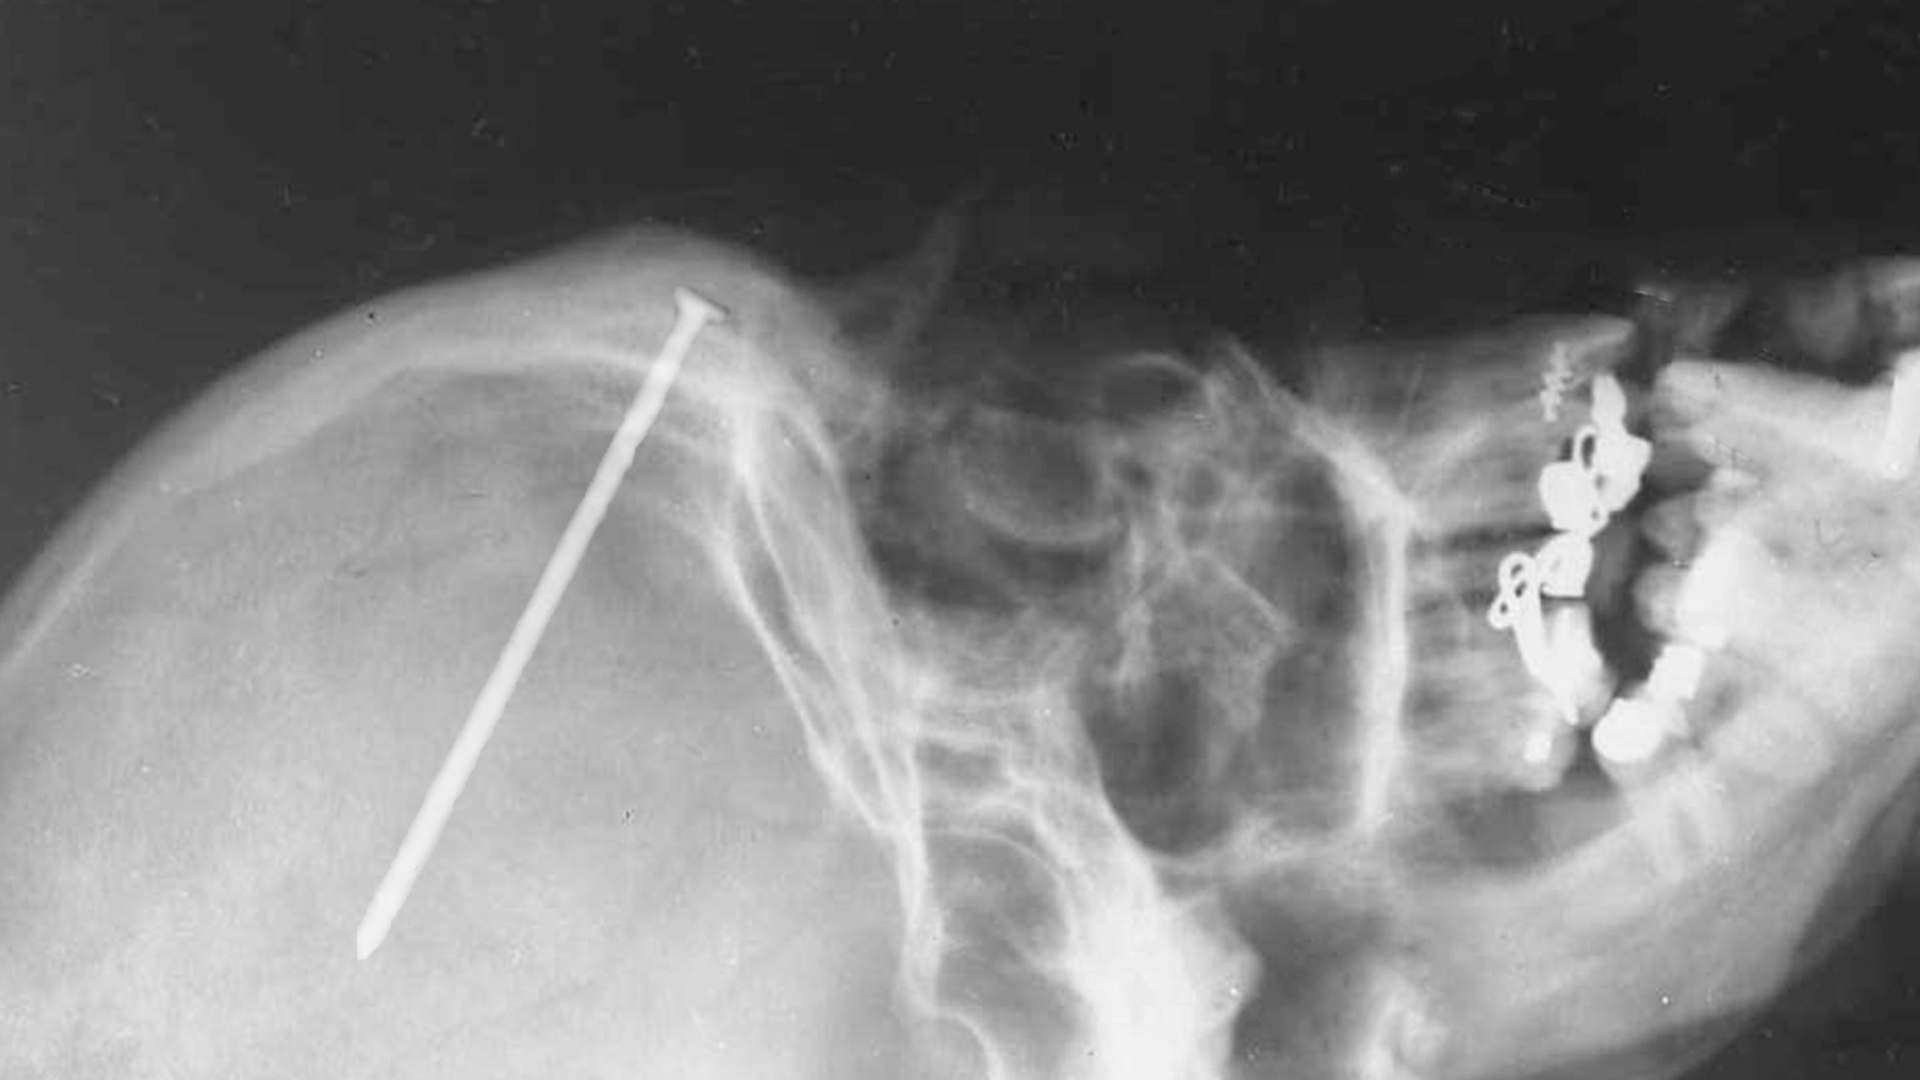

Is That A Nail In Your Head?

Is That a Nail in Your Head? is a new series that features the most shocking and incredible true stories of medical science ever caught on tape.

Featuring true stories of the most shocking medical science ever caught on tape. From a skydiver who fell onto a power line, to a man whose face was mauled off by a bear, this series tells stories of miraculous medical triumphs.